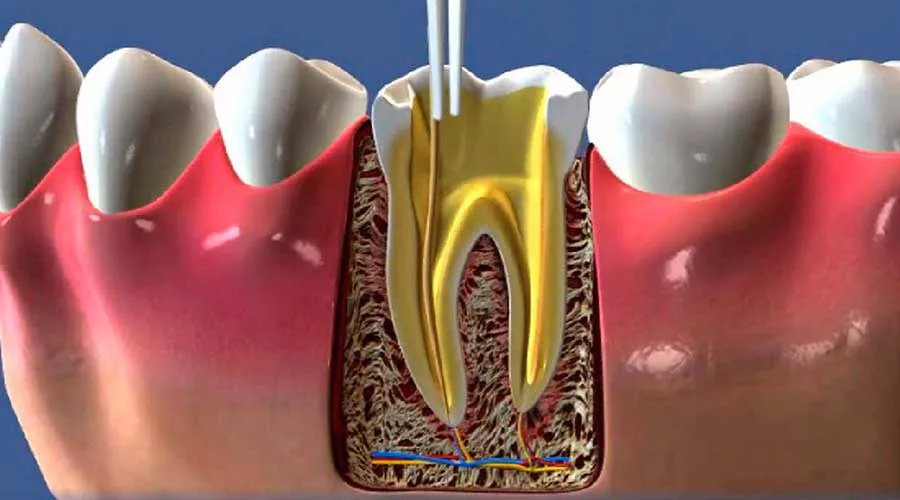

Esses profissionais são treinados para lidar com problemas complexos relacionados à polpa dentária.

O tratamento endodôntico é crucial para preservar dentes que, de outra forma, poderiam ser perdidos.

A endodontia proporciona um tratamento que visa eliminar a fonte da dor.

O tratamento endodôntico permite que dentes danificados sejam salvos.

Isso evita a necessidade de extrações e mantém a estrutura dental intacta.

Os especialistas em endodontia utilizam equipamentos modernos.

Isso inclui tecnologia de imagem e instrumentação rotatória.

Esses recursos aumentam a precisão dos tratamentos e melhoram a experiência do paciente.